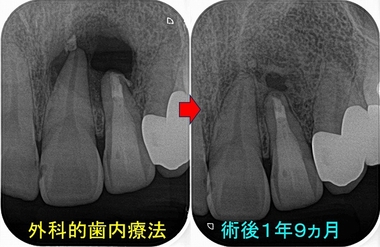

落ち着いた為か、外科後患者さんの来院がなく予後が分かりませんでしたが、

先日別件で来院されたのでレントゲンを撮りました。

腫れや症状などは一切ないそうです。

骨は出来てきてくれていますが、スルー&スルー部分の所の骨はまだ完全には骨は出来ていませんでした。

これは不完全治癒で成功に入れてもいいと思いますが、ここの骨が治るには更に時間が必要となります。